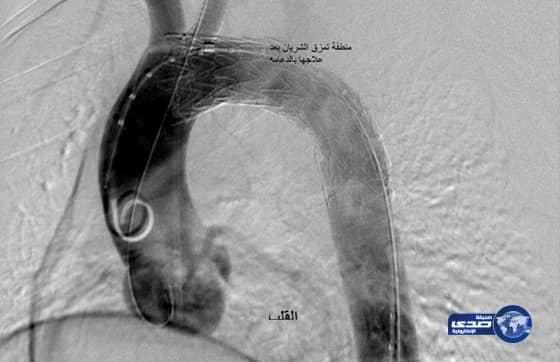

نجح فريق طبي سعودي بمستشفى الملك فهد بالمدينة المنورة في إنقاذ حياة شاب تعرض لحادث مروري عنيف نتج عنه انفجار محتوى بقوس الشريان الأورطي الصدري بالمنطقة الثانية وكسور مضاعفة بالقفص الصدري.

وأوضح رئيس الفريق الطبي الذي أجرى العملية رئيس قسم جراحة الأوعية الدموية بمستشفى الملك فهد بالمدينة المنورة بالمدينة الدكتور كمال بن أحمد زغبي أن طوارئ المستشفى استقبلت الشاب الذي كان يُعاني كذلك من كسر مضاعف بمفصل الحوض والفك العلوي, وتم التعامل مع الحالة وعمل الفحوصات و الأشعة المقطعية ثلاثية الأبعاد للشرايين بعد استقرار حالة المريض وتثبيت الكسور.

وأضاف أنه أُجريت للمصاب عملية جراحية بطريقة احترافية خلافاً للطريقة التقليدية المتبعة في مثل الحالات المشابهة وذلك من خلال تقنية المدخنة و التي تحتاج إلى مهارة و إمكانيات متقدمة لتكون بذلك أول حالة تُعالج بهذه الطريقة في منطقة الشرق الأوسط .

وأفاد الدكتور زغبي أن المتعارف عليه طبياً ارتفاع نسبة الوفاة في مثل هذه الحالات بالطريقة التقليدية المتبعة في مثل الحالات المشابهة ، لذلك رأي الفريق الطبي المعالج وضع خطة علاجية مجدولة و ذلك بإجراء العملية عن طريق وضع الدعامات اللازمة بقوس الشريان الأورطي و الشريان السباتي الأيسر المغذي للفص الأيسر من المُخ باستخدام الجراحات التداخلية عن طريق تقنية المدخنة المزدوجة والتي تتم في مراكز معدودة على مستوى أوربا و أمريكا .

وقد تمت العملية من خلال شقوق جراحية لا تتجاوز السنتمتر الواحد ليتم بعدها إيقاف النزف وعزل التمزق الشرياني عن مجرى الدم الطبيعي ليتماثل بعدها المريض للشفاء بفضل الله وتوفيقه, كما خضع بعدها لعلاج تأهيلي مكثف وهو بصدد الخروج من المستشفى و ممارسة حياته الطبيعية.